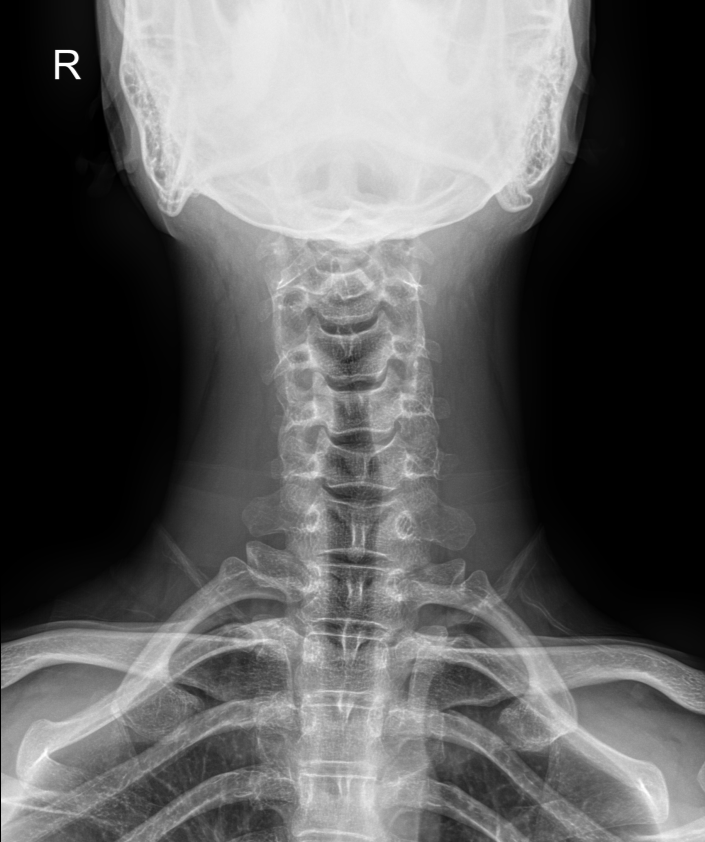

사경증으로 치료받는 환자들도 결국은 경추 측만증이라는 것을 아시는지요. 요즘 3D MRI도 나오는 시대입니다. 매우 의학적인 치료와 검사에 도움이 되고 있습니다. 사경증의 원인을 아직은 못 찾고 있지만 X-ray 검사를 해보면 역커브와 경추가 휘어있고 틀어져 있는 것을 많이 볼 수 있습니다.

사경증이 있을 때와 교정이 된 후에는 우선 먼저 증상이 없어집니다. 언제 어떻게 얼마나 사경증이 나아지는지 알 수 없지만 치료를 받는 만큼 증상이 없어지는 것은 확인이 가능합니다. 연축이 없어지고 목이 기우는 각도도 작아지고 돌아가는 정도도 점점 줄어듭니다. 치료 끝까지 목이 돌아가고 떨리는 환자도 있습니다. 이러한 증상은 아직 경추가 바르게 되지 않아서 그런 것입니다. 척추의 모양과 변형이 이렇게 중요합니다. 하지만 끝까지 교정 치료에 도전을 해서 바르게 된 후에는 여러 증상의 정도가 많이 줄어 있습니다. 이런 후에는 반드시 X-ray를 찍어서 치료의 전과 후를 비교해 보면 치료에 많은 보람이 있습니다. 측만증과 사경증, 목, 허리 디스크를 치료하기 위해서 통증부위나 문제의 부위만을 치료해서는 안된다는 것입니다. 척추의 첫 단추는 턱관절과 경추 1,2번 교정입니다. 목뼈가 빠져서 턱관절과 짝이 맞지 않으면 그 사람은 두통부터 목, 허리, 발바닥의 족저근막염까지 원인 불명의 통증으로 시달리게 됩니다. 이런저런 안 해본 치료가 없다 하는 분들 아주 많습니다. 목은 빠져있는데 밑에 척추를 아무리 치료해 준 들 시간낭비, 돈낭비만 된 것입니다. 수술해서 허리는 안 아프지만 발, 다리가 저리저리 하다는 것은 올바른 척추치료가 아니라고 생각합니다. 못 걸은 상태에서 걷는 것에 만족을 한다는 것도 매우 안타까운 치료 효과임에는 분명합니다. 우리 몸은 매우 정교합니다. 족저근막염은 원인 모를 발바닥 통증이 아니라 경추부터 허리까지 눌려내려는 압력으로 인한 방사통의 하나라는 것을 알아야 합니다. 병이 50개면 50개 약을 먹을 것이 아니라 근본원인을 알고 해결해야 하는 노력이 필요합니다. 신도림동 터커리한의원은 CBA를 이용한 턱관절 교정을 중점적으로 하고 있습니다. 사경증, 틱장애, 목디스크, 요추협착증 허리수술을 받고 난 후에도 다리가 당기고 저려서 힘든 분들은 오셔서 척추의 첫 단추부터 다시 맞추는 교정 치료를 받아보세요. 가려운 환자의 통증 부위를 시원하게 해 드릴 수 있을 것입니다.